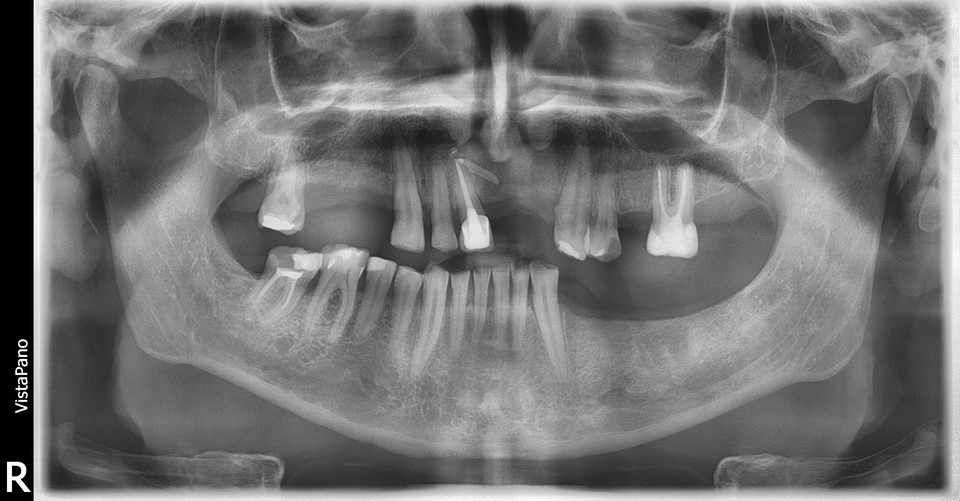

Zdjęcie pantomograficzne przedstawia brak korzenia podniebiennego w zębie trzonowym szczęki po stronie lewej